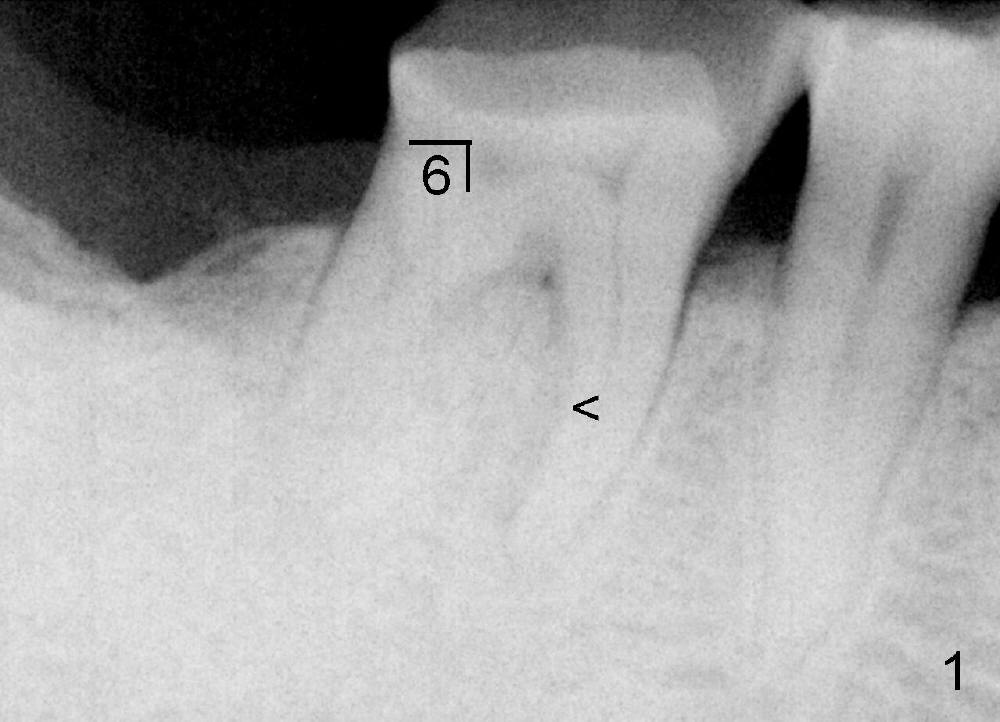

Dear Dr.魏心:马上又要上班了,再写几句。你的任何治疗方案的确定,都取决于病人的病情,病人的need and demanding 和你医生本人的技能,条件与设备等等,这儿不存在“对”与“错”的问题,从原则上来说,只是"which one is better?" 所以,大胆,细心,鼓起勇气迎接Friday, 不要忘了探查上皮附着。

如果你的最终决定是"extraction", 我觉得“delayed implantation" is much better than "immediate implantation" for this case. 因为近中肉芽可能过多,炎症反应过大,initial stability可能会有问题。